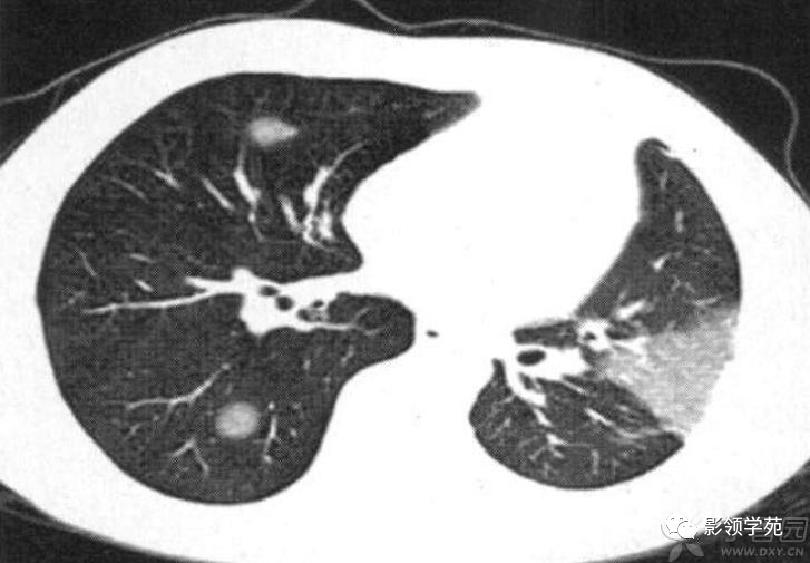

病例7:经治疗CT随访:左肺下叶片状磨玻璃密度影,右肺下叶及左肺下叶多发结节灶。

病例8:右上肺胸膜下病灶,伴厚壁空洞,邻近胸膜楔形增厚。

病例9:右下肺结节,病灶后份可见结节状钙化,边缘光滑,周围无卫星病灶。(钙化主要出现在治疗后肿块的边缘,相对较少见)